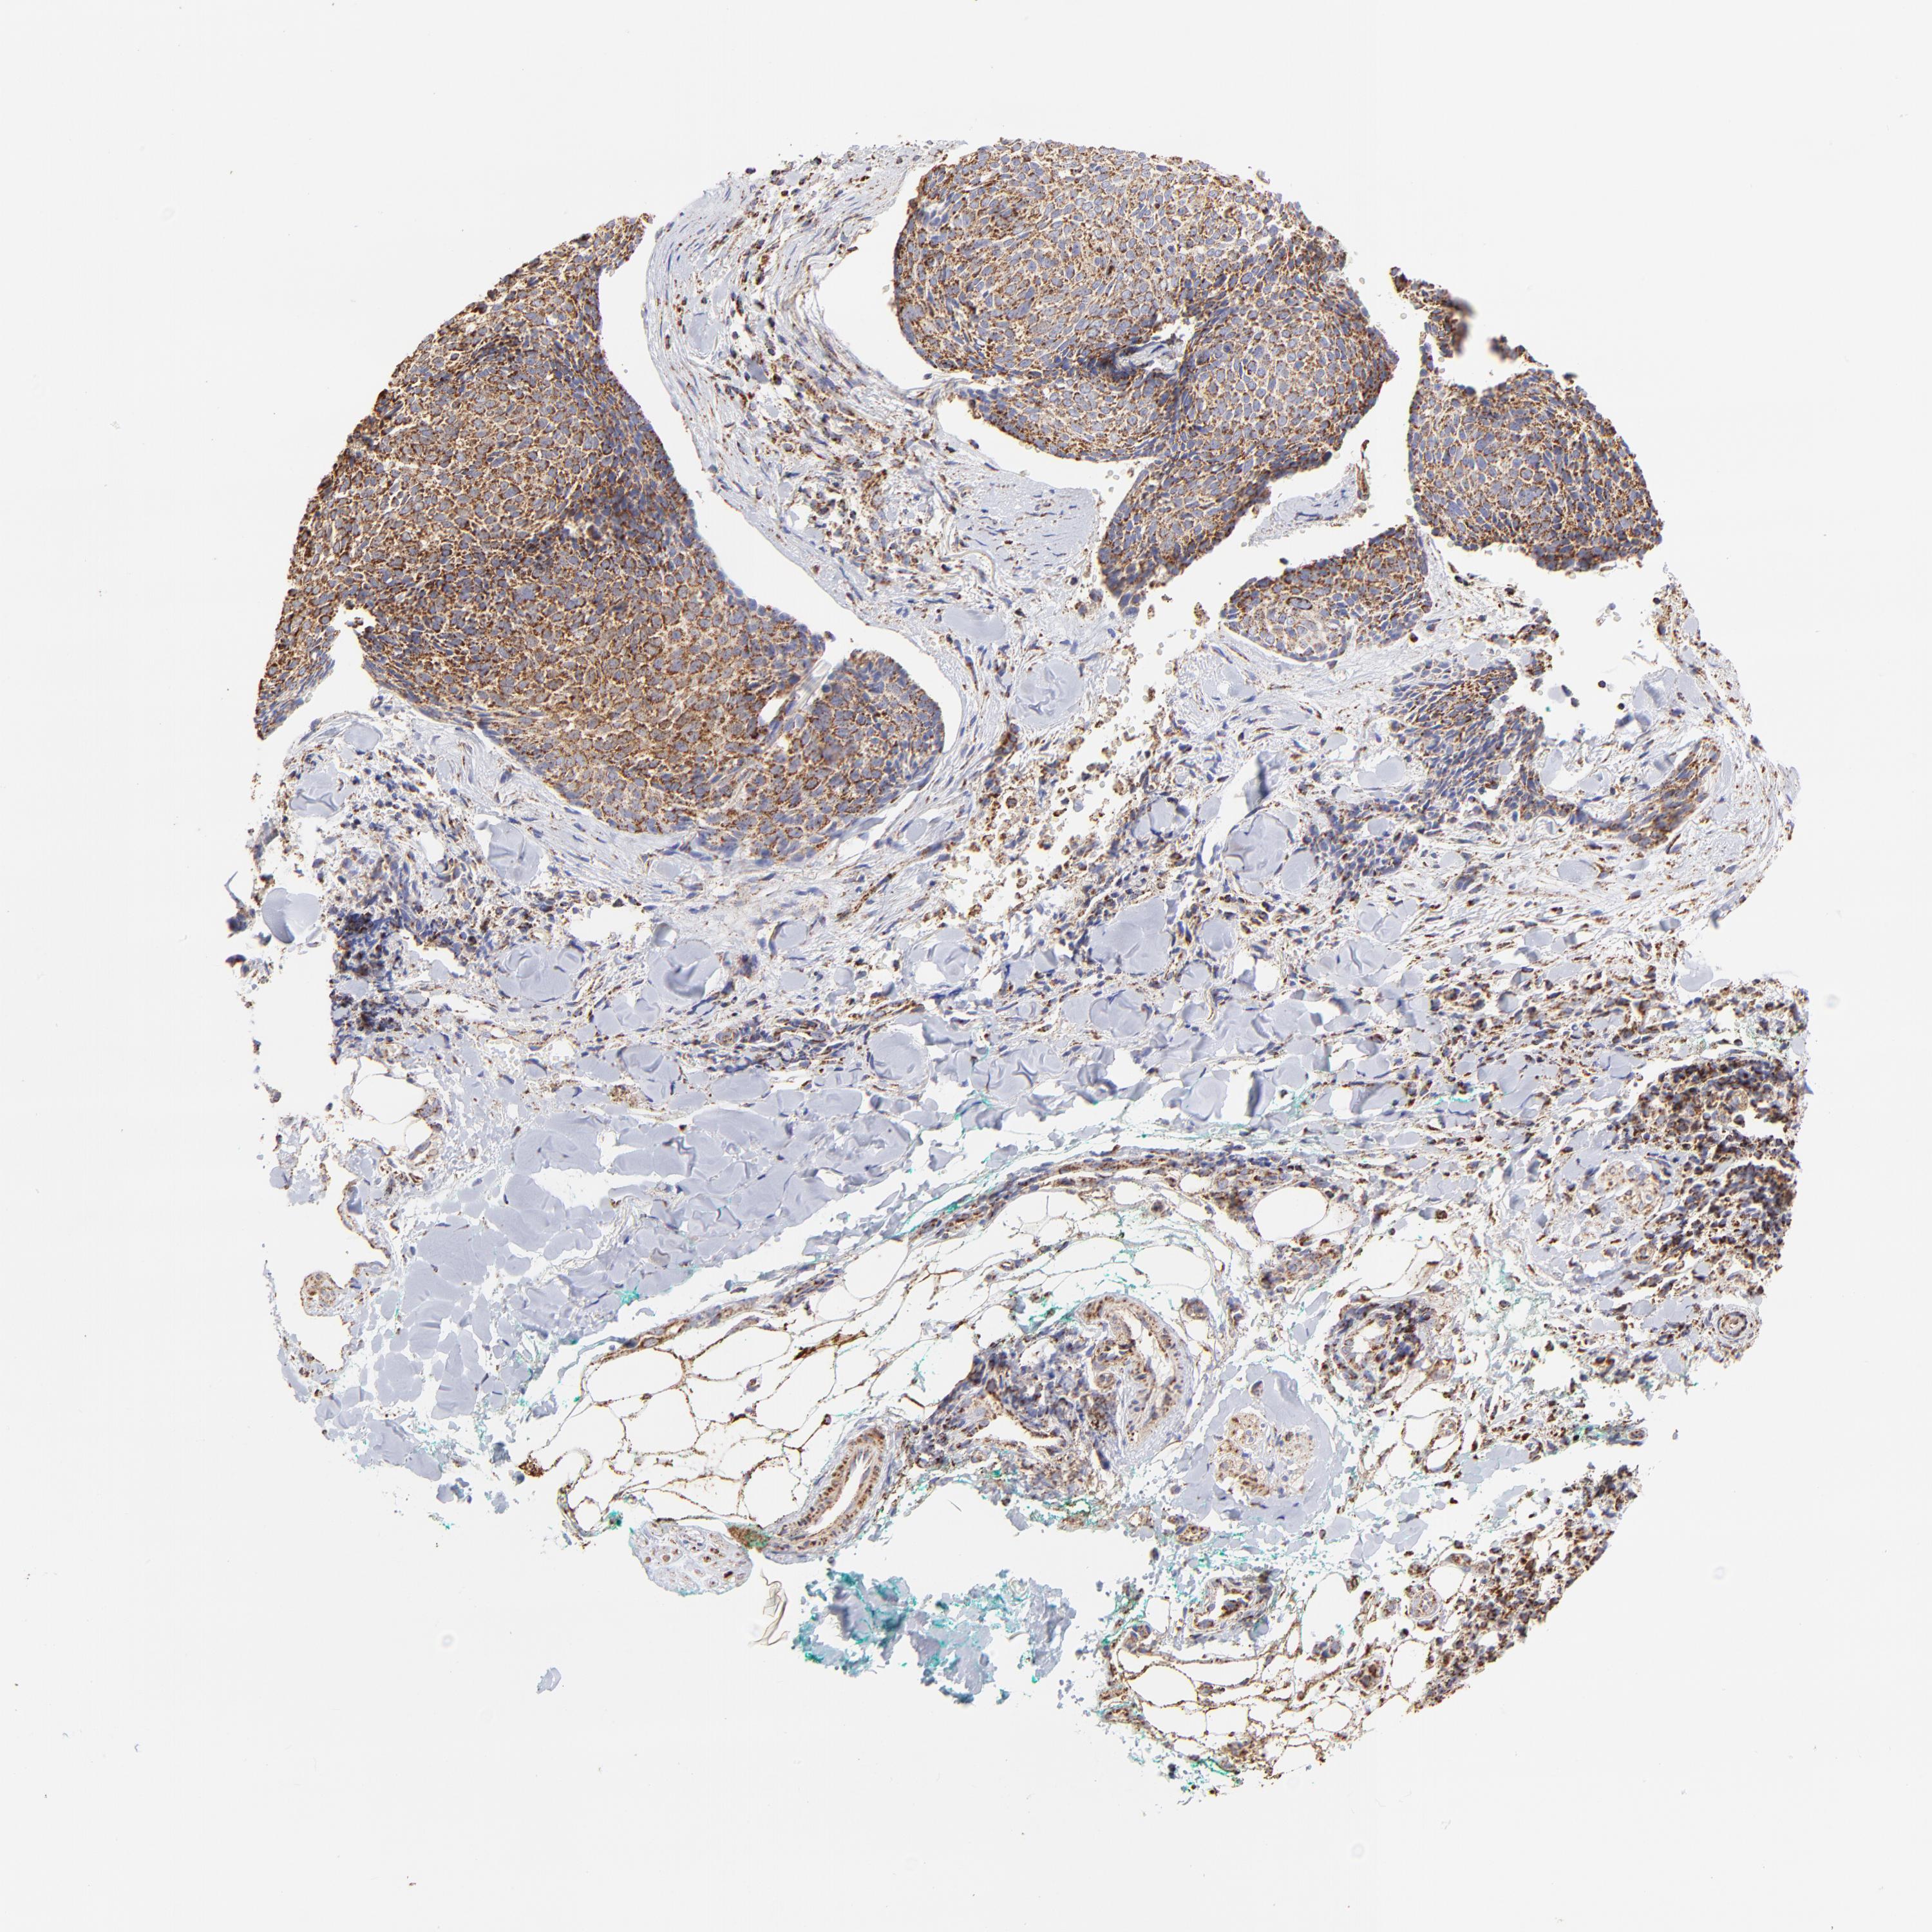

SKIN CANCER - Protein expressioni

A mouse-over function shows sample information and annotation data. Click on an image to view it in a full screen mode. Samples can be filtered based on level of antibody staining by selecting one or several of the following categories: high, medium, low and not detected. The assay and annotation is described here.

Antibody stainingi

Antibody staining in the annotated cell types in the current human tissue is reported as not detected, low, medium, or high, based on conventional immunohistochemistry profiling in selected tissues. This score is based on the combination of the staining intensity and fraction of stained cells.

Each image is clickable and will lead to virtual microscopy that enables deeper exploration of all samples and also displays staining intensity scores, fraction scores and subcellular localization as well as patient and tissue information for each sample.

Antibody HPA005835

Basal cell carcinoma